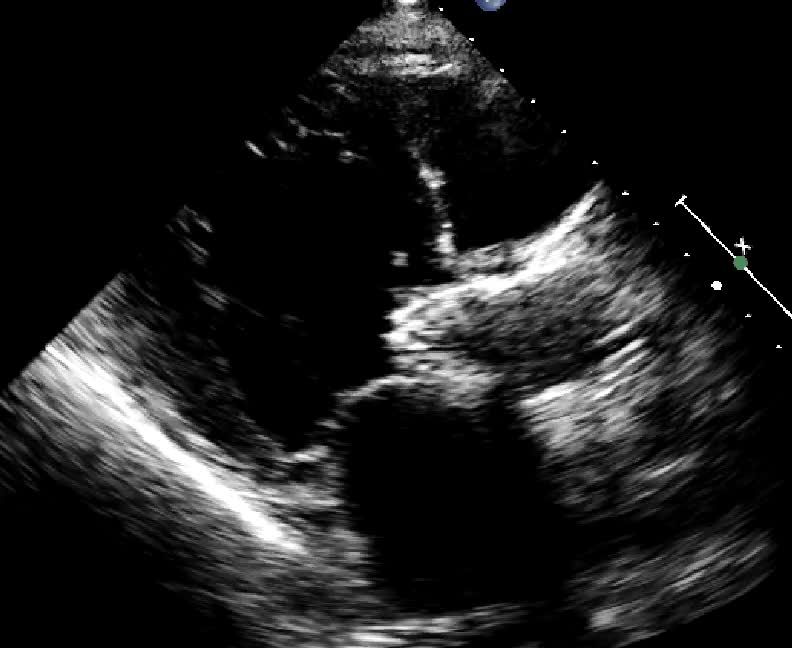

Distacco di protesi mitralica biologica

Autore:

Manuela Muratori